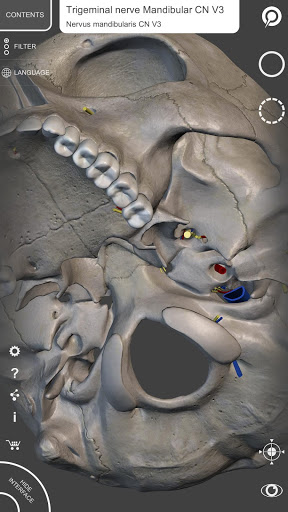

Mỗi xương của bộ xương người đã được tái tạo ở dạng 3D, bạn có thể xoay và phóng to từng mô hình và quan sát chi tiết từ mọi góc độ.

Bằng cách chọn mô hình hoặc ghim, bạn sẽ được hiển thị các thuật ngữ liên quan đến bất kỳ bộ phận giải phẫu cụ thể nào, bạn có thể chọn từ 12 ngôn ngữ và hiển thị các thuật ngữ bằng hai ngôn ngữ cùng lúc.

HÌNH GIẢI PHẪU 3D CÓ ĐỘ CHI TIẾT CAO

• Hệ thống xương

• Mô hình 3D chính xác

• Bề mặt của bộ xương có kết cấu độ phân giải cao lên đến 4K

• Xoay và Phóng to mọi mô hình trong không gian 3D

• Ghim tương tác cho phép trực quan hóa thuật ngữ liên quan đến mọi chi tiết giải phẫu